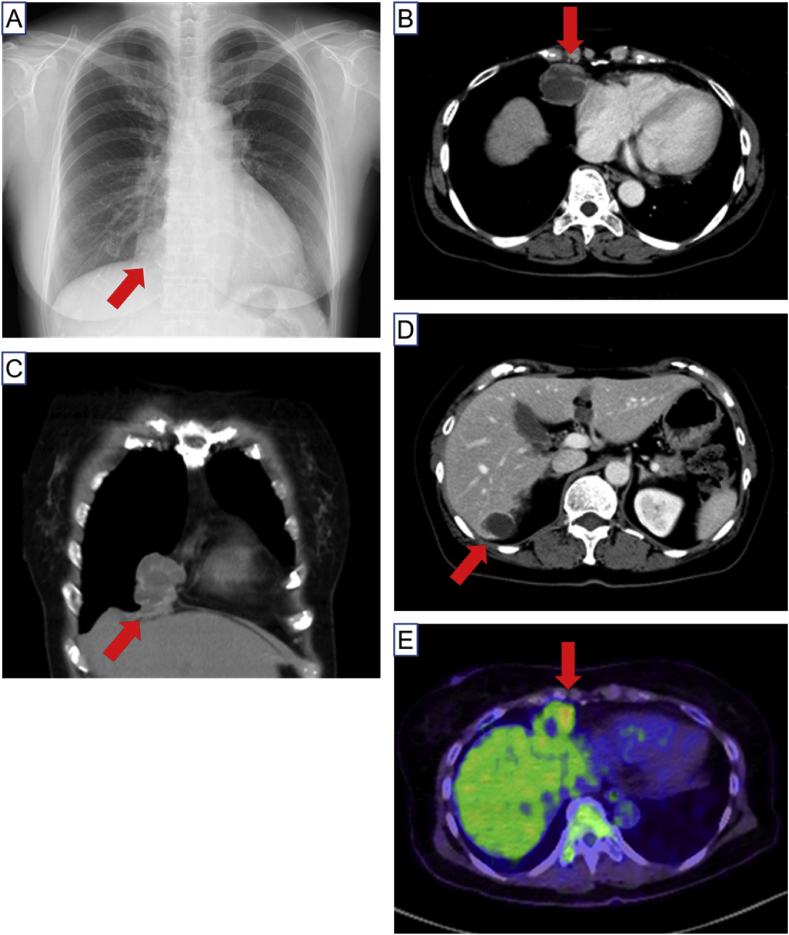

Physical examination of the patient was normal. Chest X-ray showed a sole nodular lesion adjacent to heart in right lower lung field, and contrast-enhanced computed tomography revealed a multiloculated cystic heterogeneous mass in anterior mediastinum and liver (Fig. 1A–D). A positron emission tomography revealed a higher standardized uptake value, ranging 2.6 to 4.2 of maximum value, of cystic wall, suggesting a possibility of malignancy in the lesion (Fig. 1E). The serum marker CA 125 was 33.9 U/mL within normal range. Since bronchoscopic study could not reach the mediastinal mass, the patient underwent resection of the mediastinal tumor by right video-assisted thoracic surgery (VATS).

Fig. 1.

A, Chest X-ray showed a sole nodular lesion (arrow) adjacent to heart in right lower lung fields. B and C, Chest contrast-enhanced computed tomography shows a multiloculated cystic heterogeneous mass (arrow) in anterior mediastinum. D, A multiloculated cystic heterogeneous mass is also shown in liver (arrow). E, A positron emission tomography revealed a higher standardized uptake value of the mediastinal mass (arrow).